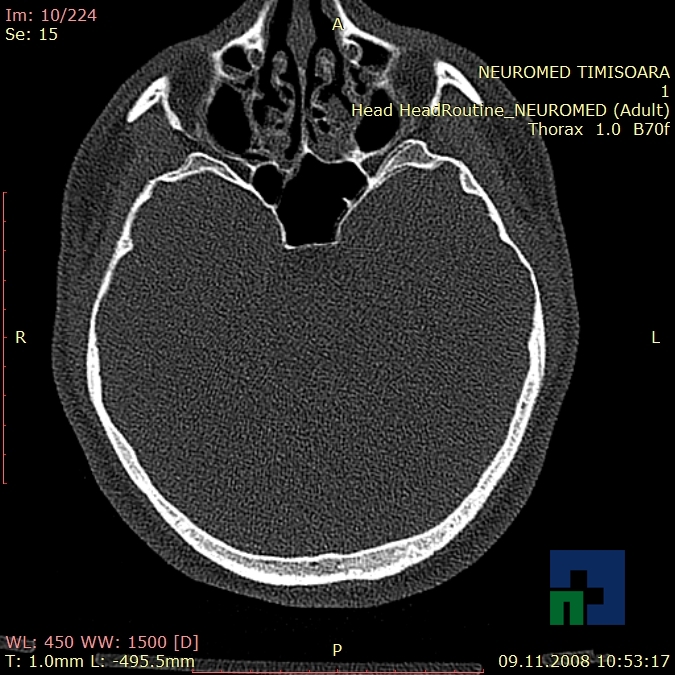

În cazul traumatismelor cranio-cerebrale:

- Diagnosticul traumatismelor de bază de craniu

- Diagnosticul fracturilor:

- Unice

- Multiple

- Cu înfundare

- Complexe cranio-sinusale

- Complexe cranio-etmoidale

- Complexe cranio-orbitare

- Complexe cranio-faciale